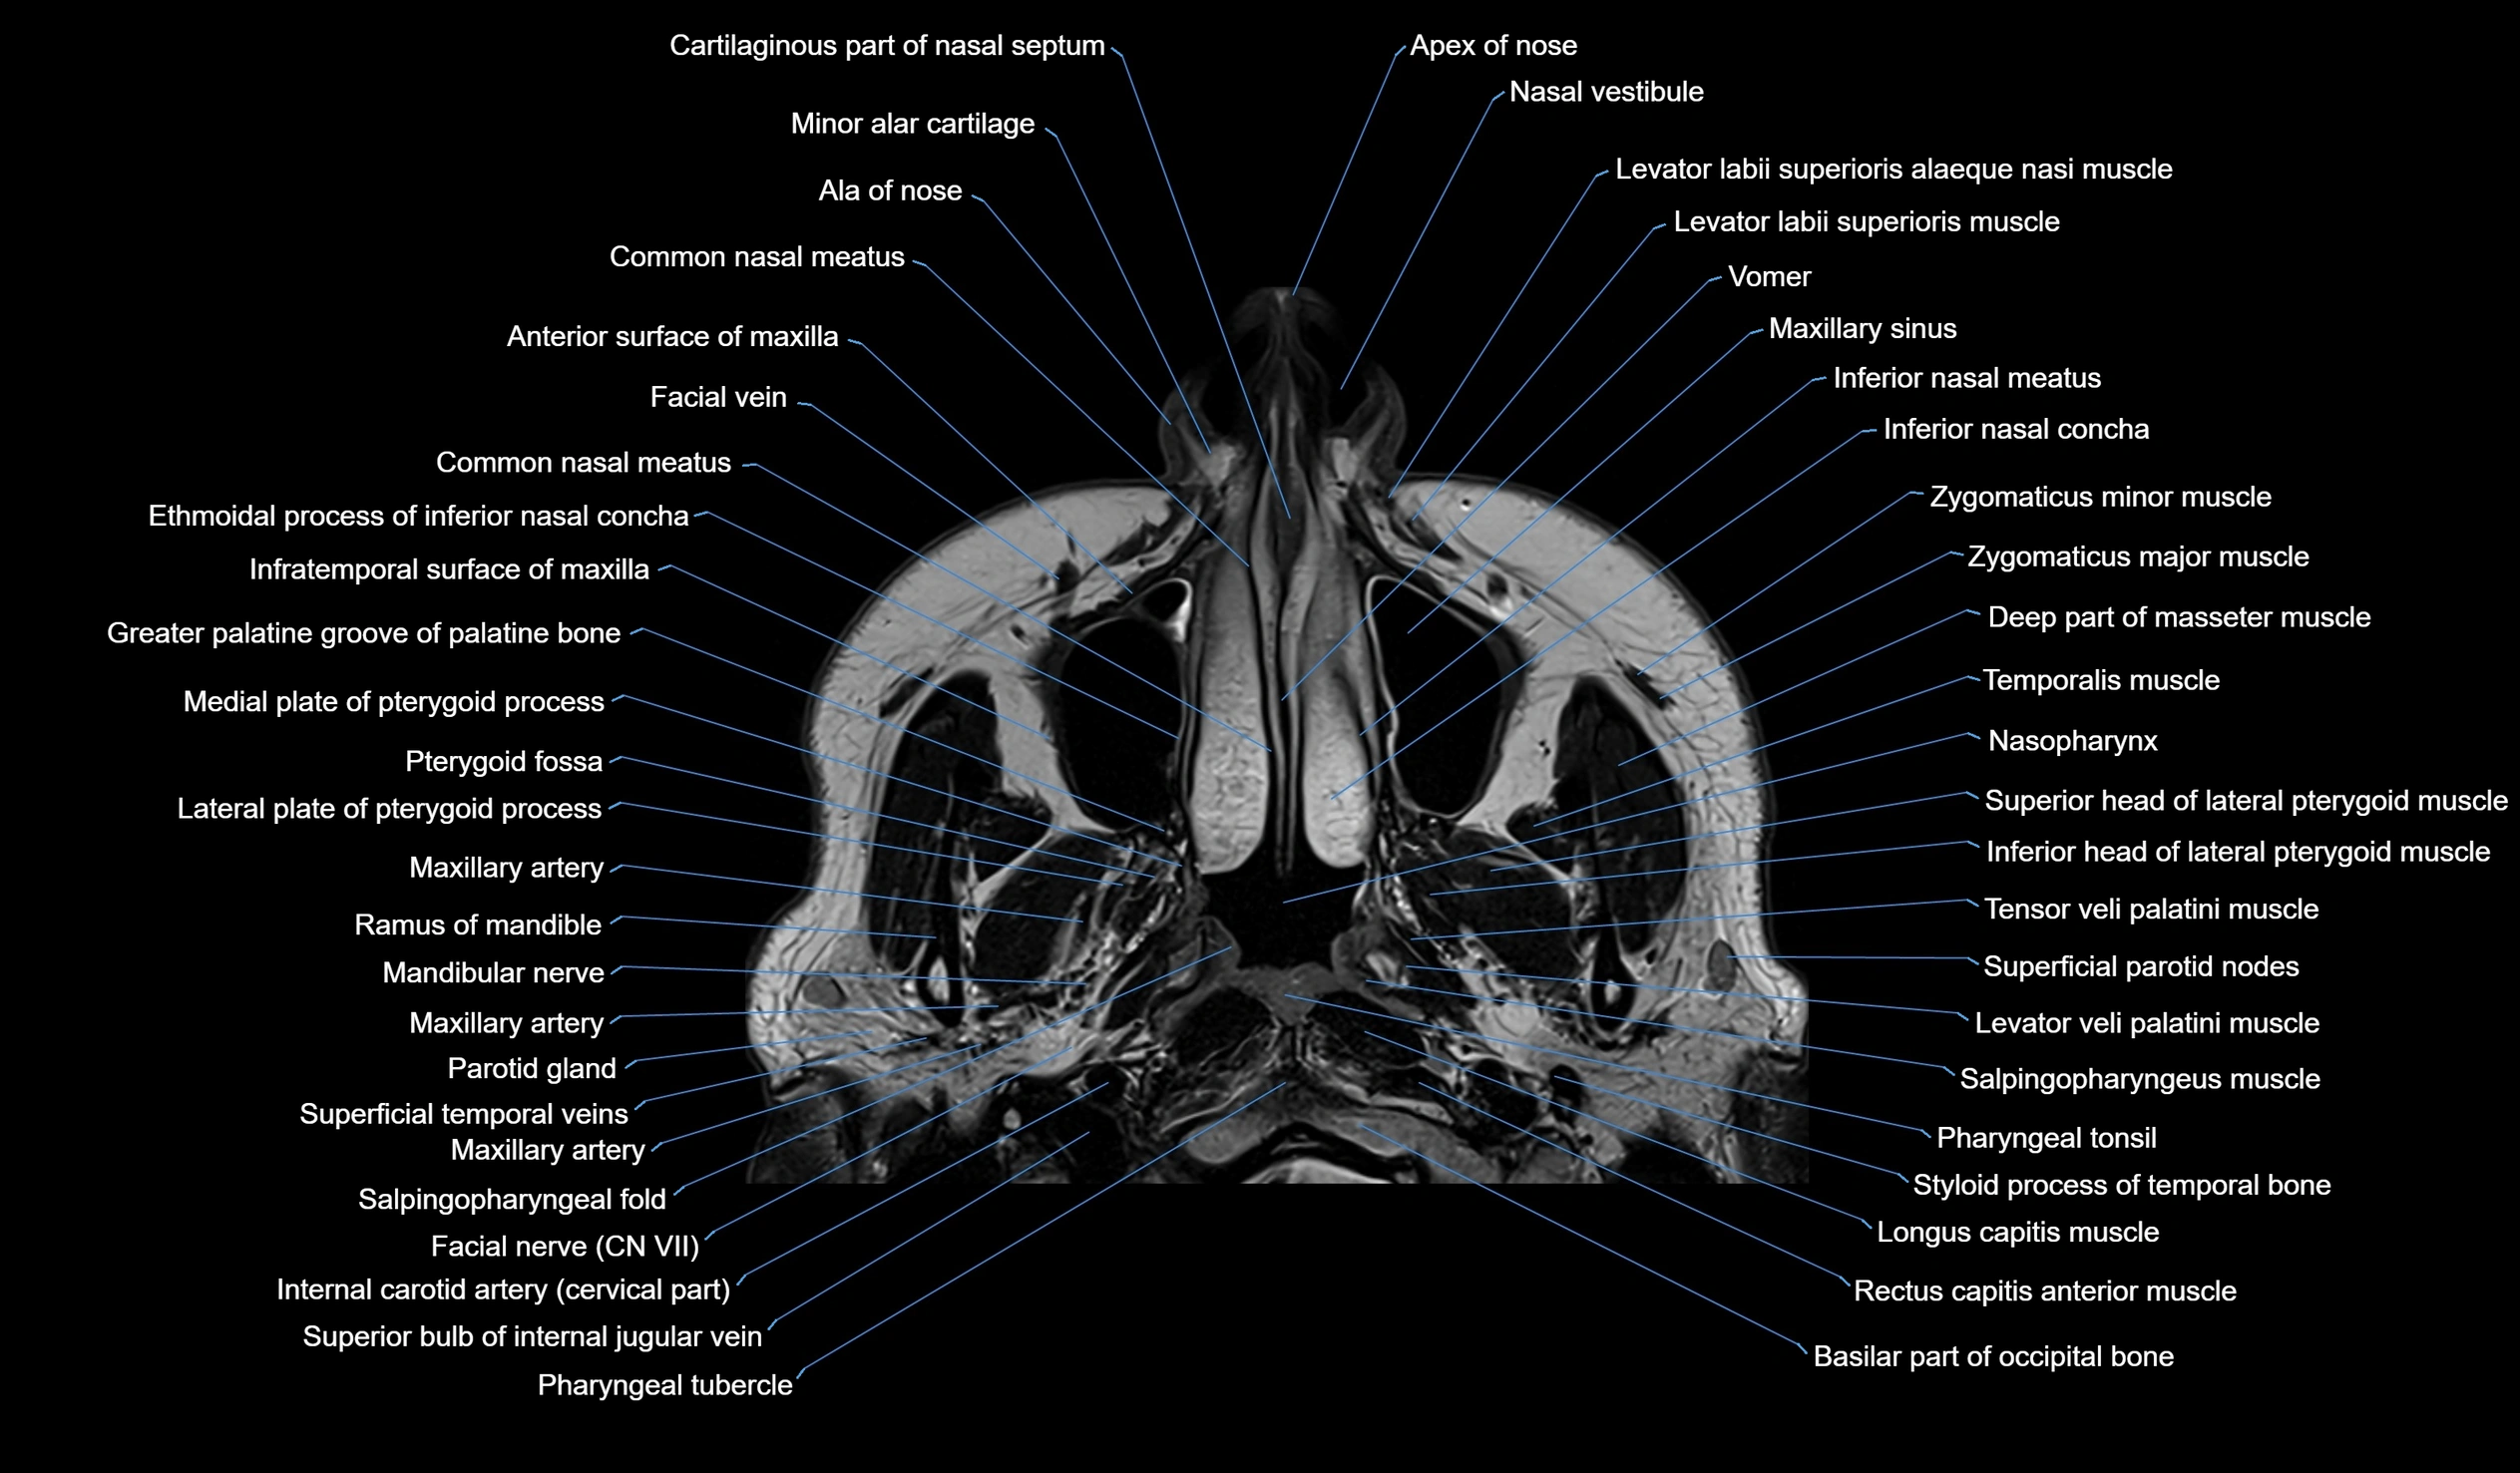

MRI images